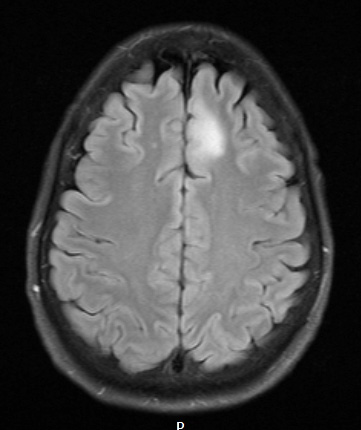

Case 10 History ---- The patient is a 53-year-old woman with a six month history of headaches unrelieved by medications and an increasing feeling of pressure behind her eyes. MRI showed a T2/FLAIR expansile cortically based lesion within the medial left frontal lobe with no corresponding enhancement or increased relative cerebral blood volume on perfusion studies. Radiological impression: Favor low grade glioma. ---- 10A1 There is a small hyperintense mass demonstrated in the left medial frontal lobe on this FLAIR exam.